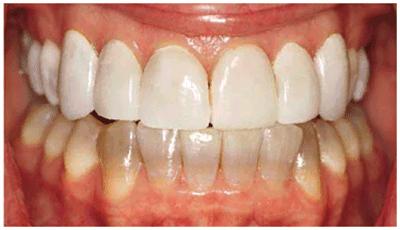

chromogenic foods, and beverages (Figures 16-16A 16-16B 16-17A, and 16-17B). Although these types of stains

generally require only 2 to 6 weeks of bleaching treatment, some are more

Figure 16-16A: Some teeth darken over time from chromagenic foods. Some patients' teeth are just naturally yellow.

Figure 16-16B: Whitening of the maxillary teeth using 10% carbamide peroxide in a custom tray results in a more pleasing smile. This patient is now interested in closing the spaces.

Figure 16-17A: Some teeth darken through natural aging.

Figure 16-17B: Whitening of the maxillary teeth using 10% carbamide peroxide in a custom tray produces a normal progression of color from gingival to incisal edge but offers a more pleasing, younger look to the patient.